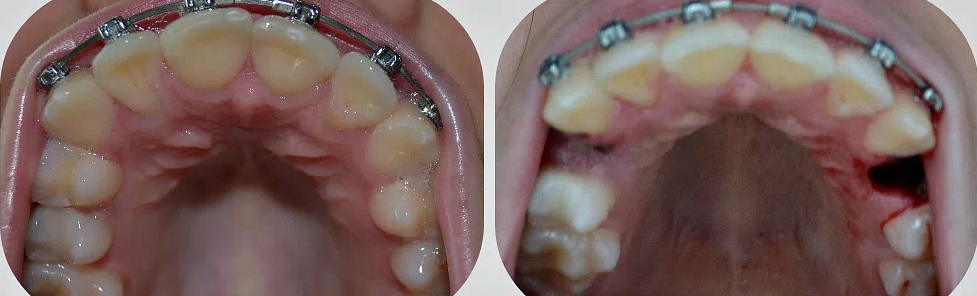

Удаление верхнего зуба мудрости: фото до и после

Особенно опасны случаи, когда восьмерка начинает расти «в бок» и давит коронкой в зубной ряд. В необходимо удаление зуба мудрости на верхней челюсти, иначе последствия могут быть самыми неприятными. Дополнительная нагрузка на соседний зуб приводит к разрушению эмали. А если давление слишком велико, может произойти «цепная реакция», результатом которой является смещение всех зубов в ряду.